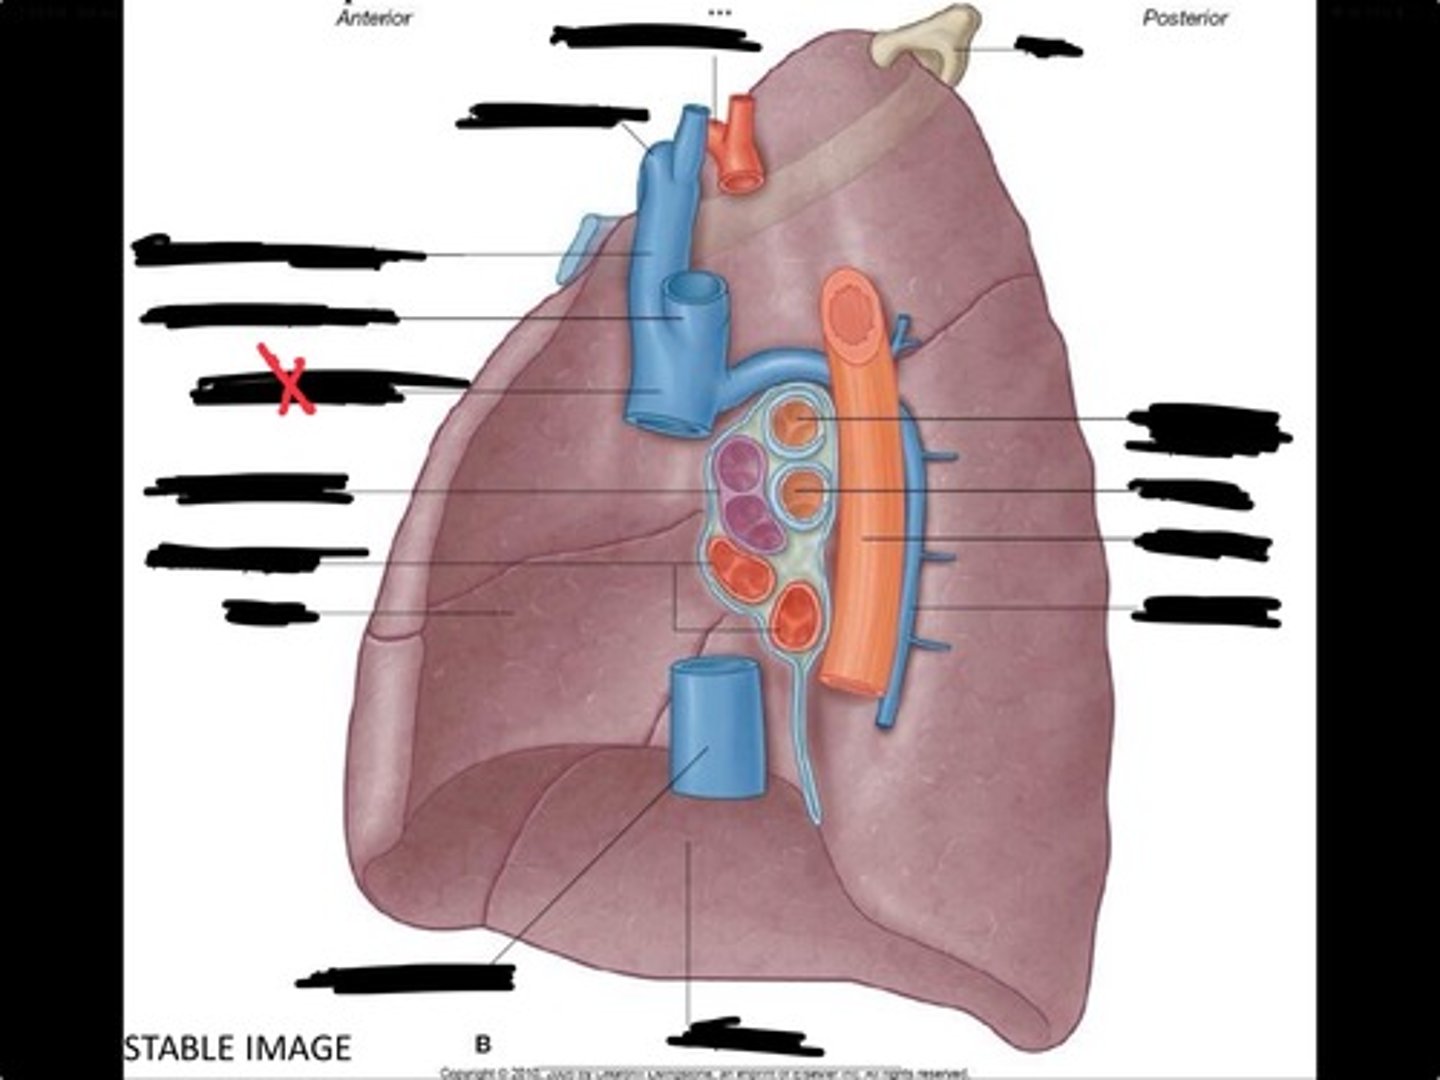

Rib 1

Pulmonary artery

Bronchus to superior lobe

Pulmonary veins